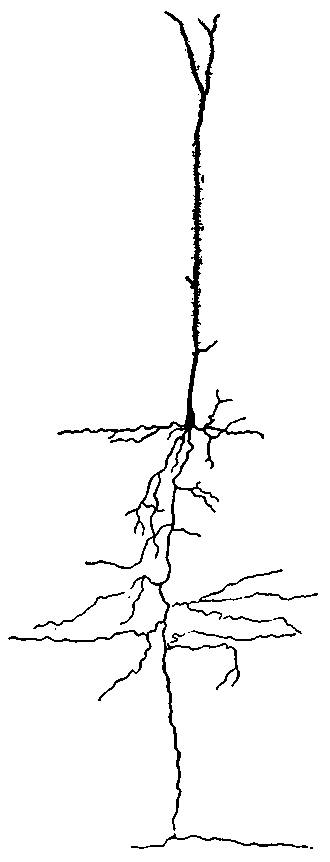

| 2. | Cortex of human brain illustrating complexity of the systems and plexuses of nerve fibers | 109 |

| 8. | Scheme of lower motor neuron | 114 |

| 11. | Isolated cell from human spinal cord | 117 |

| 12. | Neuron from the optic lobe of the embryo chick | 118 |

| 22. | Motor cell of ventral horn of spinal cord from the human fetus | 133 |